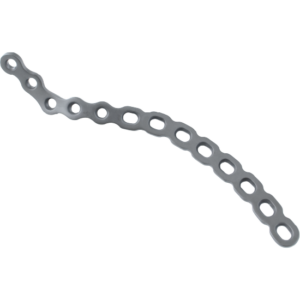

Curved Reconstruction Plates